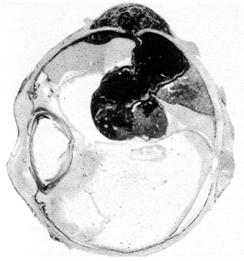

sinechiile iriene posterioare (irido-cristaliniene) reprezinta aderente ale marginii pupilare la cristaloida anterioara, datorita fibrinei si celulelor inflamatorii din umoarea apoasa (Fig. 12.2). Acestea au un aspect dintat (la inceput) si determina deformarea pupilei (vezi plansa), ele putand fi indepartate prin dilatarea pupilei cu instalatii de coliruri midriatice (atropina solutie 1%).

Fig. 12.2 - Sinechii iriene